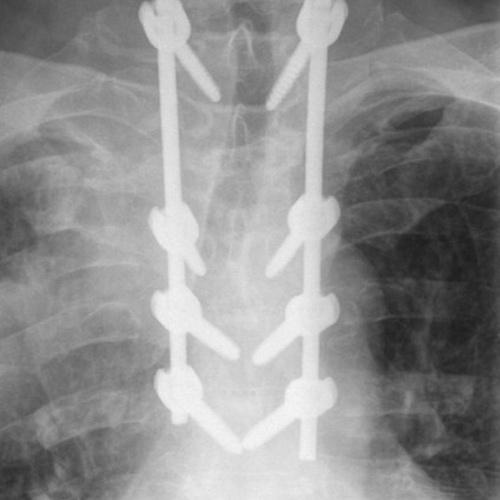

Spinal stenosis (Lumbar) Spinal stenosis (Cervical) Spinal stenosis (Thoracic) Lumbar Disc Herniation Spondylolisthesis Cervical Foraminal Stenosis Vertebroplasty Lumbar Fusion Anterior Cervical Fusion (ACDF) Posterior Cervical Fusion Thoracic Fusion Revision Lumbar Fusion Surgery Facet Joint Cyst Spinal Tumour Minimally Invasive Lumbar Fusion (XLIF) Minimally Invasive Lumbar Fusion (ALIF) Lumbar Fusion (TLIF) Thoraco-lumbar Fusion Lumbar Corpectomy Complex Lumbar Spine Surgery (Spino-pelvic fixation) Complex Cervical Spine Surgery Complex Thoracic Spine Surgery Occipito-cervical Fusion Minimally invasive surgery for thoracic disc herniation Other Related Topics